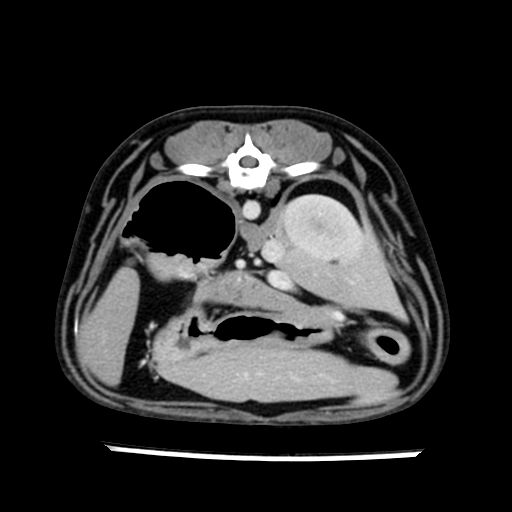

prescritto esame TAC

sequenza immagini limitata al fegato reni e surreni

le immagini ecografiche rispetto alla tac datano circa 7 mesi prima ,le surrenali sono normali nonostante il test acth sia risultato positivo .all’esame TAC dopo diversi mesi risultano aumentate armonicamente nel volume e si individua un forte sospetto di adenoma ipofisario .

sospetto adenoma ipofisario vs. meno probabilmente meningioma della base; intertiziopatia polmonare; lesione espansiva epatica, verosimilmente del lobo laterale sinistro, di sospetta natura neoplastica; lesioni spleniche di natura da definire; iperplasia/ipertrofia delle ghiandole surrenali, bilateralmente; vertebra di transizione del rachide toracico; tenosinovite cronica del muscolo bicipite brachiale di destra.

- Nessuna informazione diversa per quello che riguarda l’esame ecografico del fegato e la presa del contrasto si confermano le lesioni individuate e l’ipoenanchement in fase portale.

- la total body permette di escludere metastasi e di avvicinarsi all’interventistica